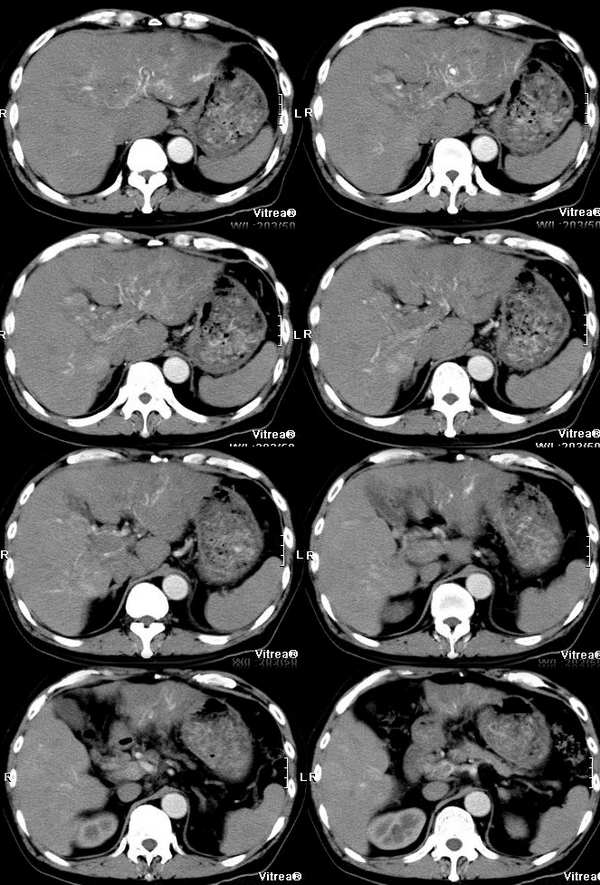

男性,58岁,肝硬化数年,近几个月出现黄疸,腹胀,食欲下降,尤其双下肢浮肿明显。超声提示肝脏多个结节。ct三期扫描图像如下:

门脉期:

肝静脉:在动脉期的第一张图片上就可以看到右心房的充盈缺损和下腔静脉近心段的明显增粗,增粗的下腔静脉内部可以见到点状、条状的强化血管影,这些强化的血管影是什么来源?这些高密度影蜿蜒曲折,和主动脉同时显影,所以只能考虑为主动脉的分支血管之一。到门脉期和平衡期,右心房的充盈缺损更加明显了,肝静脉和下腔静脉的强化非常微弱,肝段下腔静脉的管腔十分狭窄,但肝外段的下腔静脉明显的饱满,这是由于右心房的充盈缺损和下腔静脉近心段的栓子梗阻造成的。在动脉期肝左叶有一条横行血管也非常引人注目,考虑为肝左静脉的可能,但其汇入腔静脉端呈一盲端,估计终止于栓子部位,该血管的过早显影提示存在动静脉分流,从病因上来说以原发性肝癌最为常见。在临床上,该患者有双下肢明显的浮肿,要用下腔静脉的梗阻来解释。

门静脉:门静脉不论在门静脉期还是实质期(其实对于这个病人来说,我们平常所说的门静脉期还是实质期已经不适用了)均未见显影,在实质期反而发现门静脉和周围密度增高的肝实质相比呈低密度,这说明门静脉主干和主要分支均形成栓子。由于正常情况下,肝脏的大部分血供来自门静脉,这就造成了肝脏的强化幅度明显下降。在胰头勾突前方可以见到扩张的血管分支,应该为门静脉的侧枝循环血管,但是奇怪的一点是脾脏不大,不太好解释。

肝实质:该患者既有门静脉供血的下降又有肝静脉的回流异常,形成了比较复杂的强化效果。由于门静脉为入肝血管,它的梗阻造成肝脏的强化幅度明显下降,但在延迟扫描时,其引流范围内的血液会经过侧枝循环逐渐进入,所以其密度会缓慢地上升。另外又由于肝静脉的回流异常,会引起布查氏综合征的密度改变,造成肝实质密度不均匀。

肿瘤:由于肝脏本身存在血液循环的异常,所以肿瘤的血供也会受到影响。该患者在动脉期肝左叶见到明显扩张的肝动脉分支和肝左静脉的早期显影,强烈提示左叶病变。尽管没有见到明显的动脉期肿瘤强化,但仔细观察还是有动脉供血病变的,不过密度较淡,边缘模糊;在平衡期,左叶肿瘤露出其真面目,和肝脏实质相比呈低密度。由于患者有多年肝硬化病史和存在动静脉分流和静脉栓子,综合考虑还是应该首先考虑为原发性肝癌。另外腔静脉内栓子动脉期明显动脉供血,也是肝癌癌栓的特征,这一点和hejie的意见不同。

肝脏超声提示多发占位,仔细观察动脉期在肝脏左右叶交界和肝右叶后段均可以见到小片状强化,尽管不很典型也应该考虑为癌瘤,由于肝脏多发的癌瘤,造成了门静脉、肝静脉系的广泛癌栓。